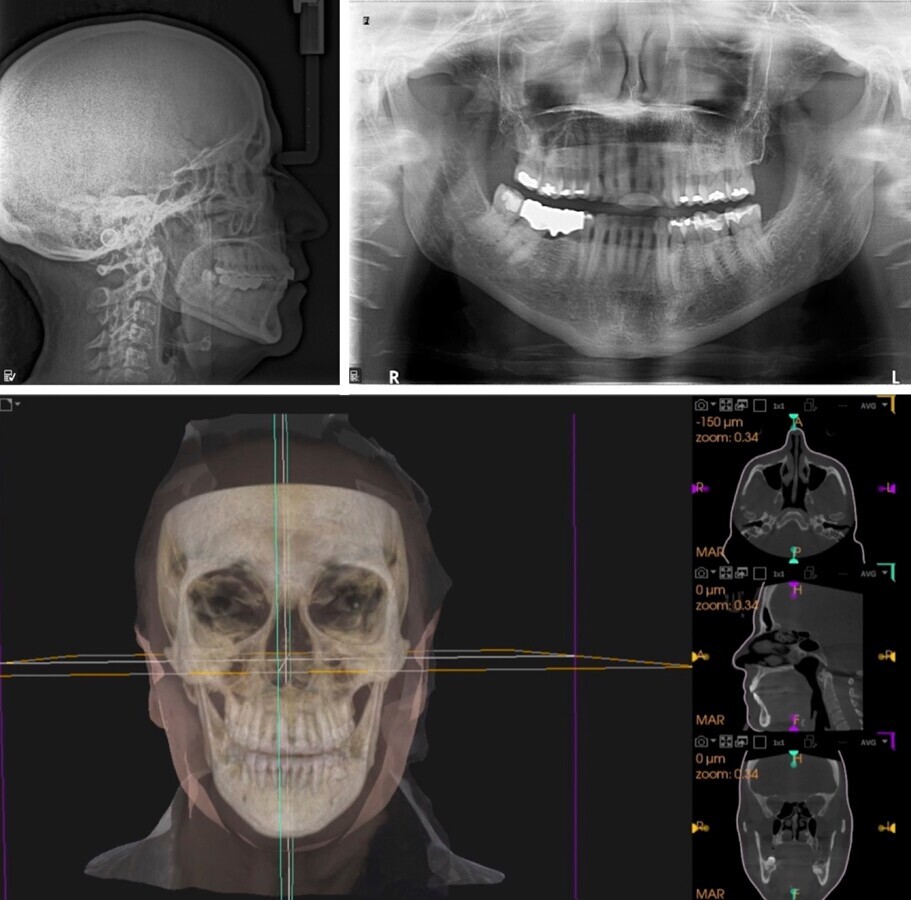

En el diagnóstico dental se observan en radiografías y tomografías una excelente condición periodontal y radicular para el soporte del Dispositivo de Avance Mandibular, así como vías aéreas estrechas a nivel de la faringe (Figura 2).

Figura 2. La paciente presentaba buen soporte periodontal para el DAM y vías aéreas estrechas a nivel de la faringe

En el análisis de ATM todos los estudios muestran un funcionamiento normal en la rotación y translación del cóndilo en su Cavidad Glenoidea, siendo buena opción de tratamiento el DAM (Figura 3).